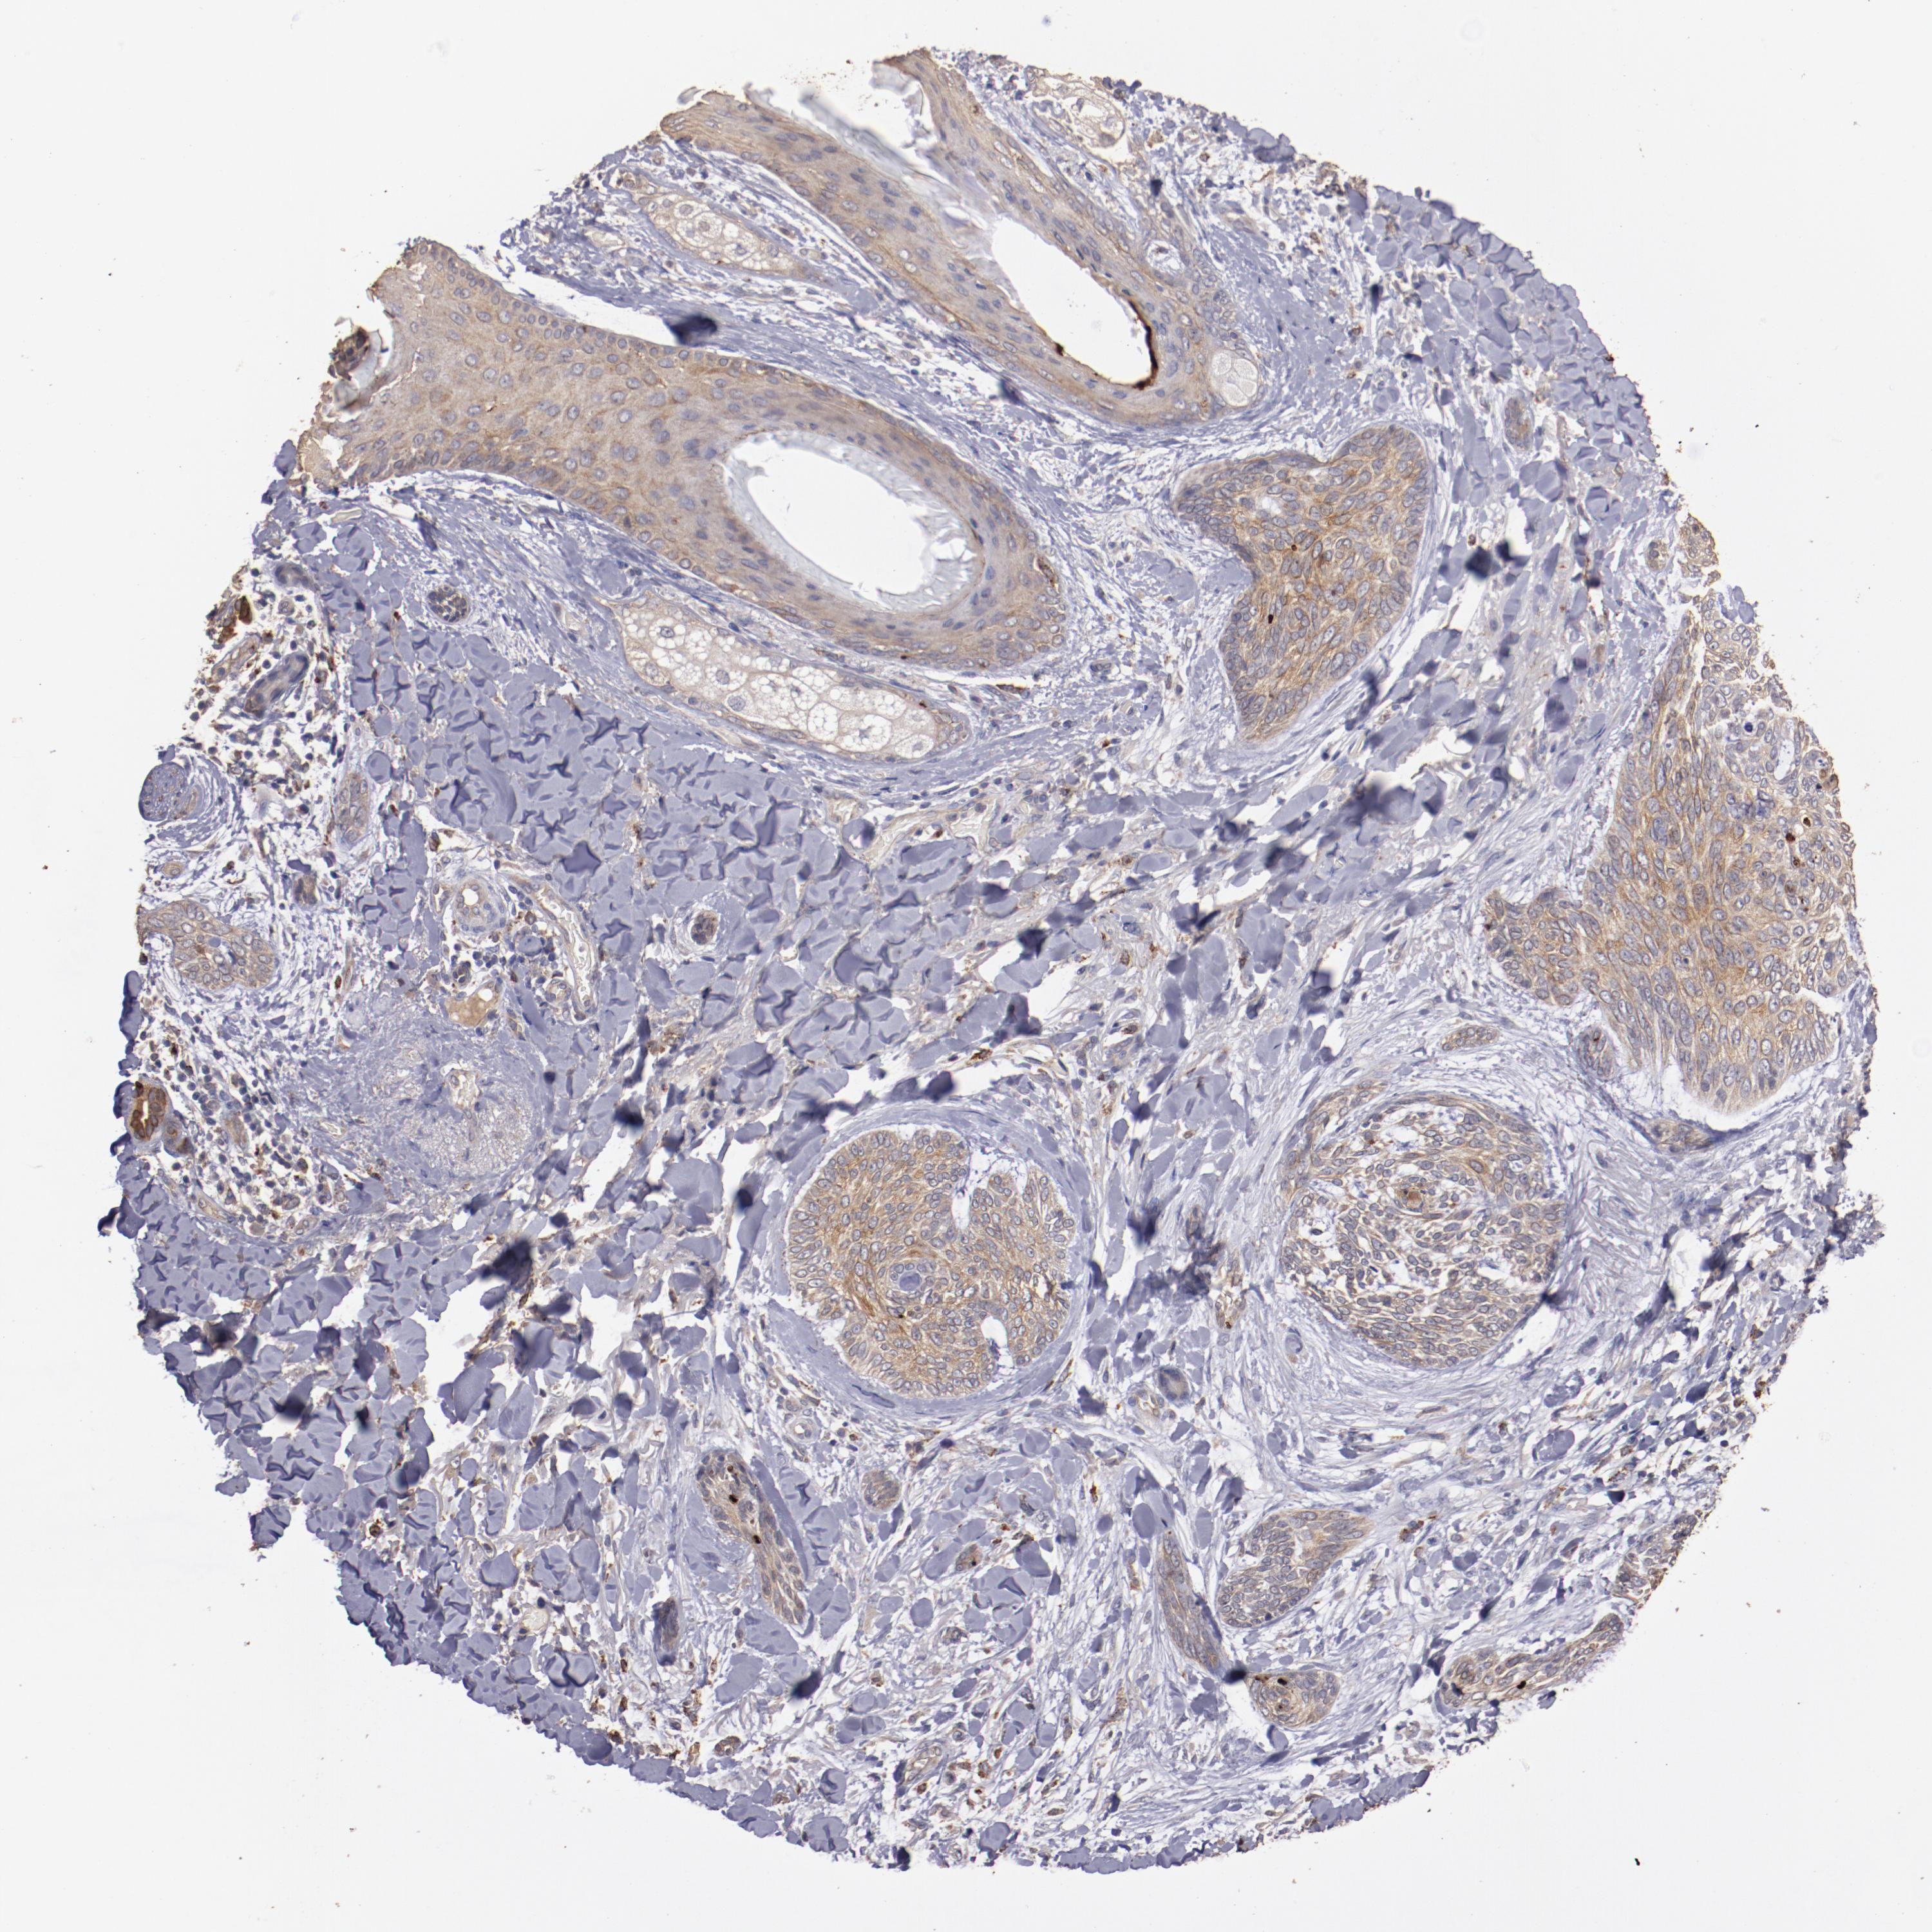

SKIN CANCER - Protein expressioni

A mouse-over function shows sample information and annotation data. Click on an image to view it in a full screen mode. Samples can be filtered based on level of antibody staining by selecting one or several of the following categories: high, medium, low and not detected. The assay and annotation is described here.

Each image is clickable and will lead to virtual microscopy that enables deeper exploration of all samples and also displays staining intensity scores, fraction scores and subcellular localization as well as patient and tissue information for each sample.

Antibody HPA002945

Staining

High

Medium

Low

Not detected

Intensity

Strong

Moderate

Weak

Negative

Quantity

>75%

75%-25%

<25%

None

Location

Nuclear

Cytoplasmic/membranous

Cytoplasmic/membranous,nuclear

Squamous cell carcinoma, NOS

Basal cell carcinoma